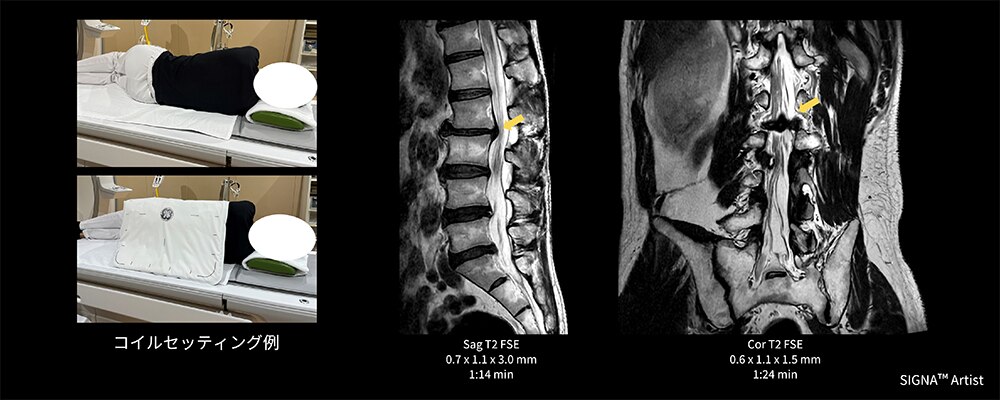

Case1 側臥位の腰椎検査

60代の男性。椎間板ヘルニアにて経過観察のため腰椎MRI検査を実施。検査当日痛みが強く、仰臥位困難なため側臥位にて検査施行(図3)。そこで、AIR™ Coilの向きを変えて使用し腰部全体にコイルをフィットさせ覆うことが出来た結果、通常の検査と遜色ない画像を取得でき、診断に貢献できた一例。

図3 側臥位の腰椎検査におけるAIR™ Coilのセッティング例と臨床画像